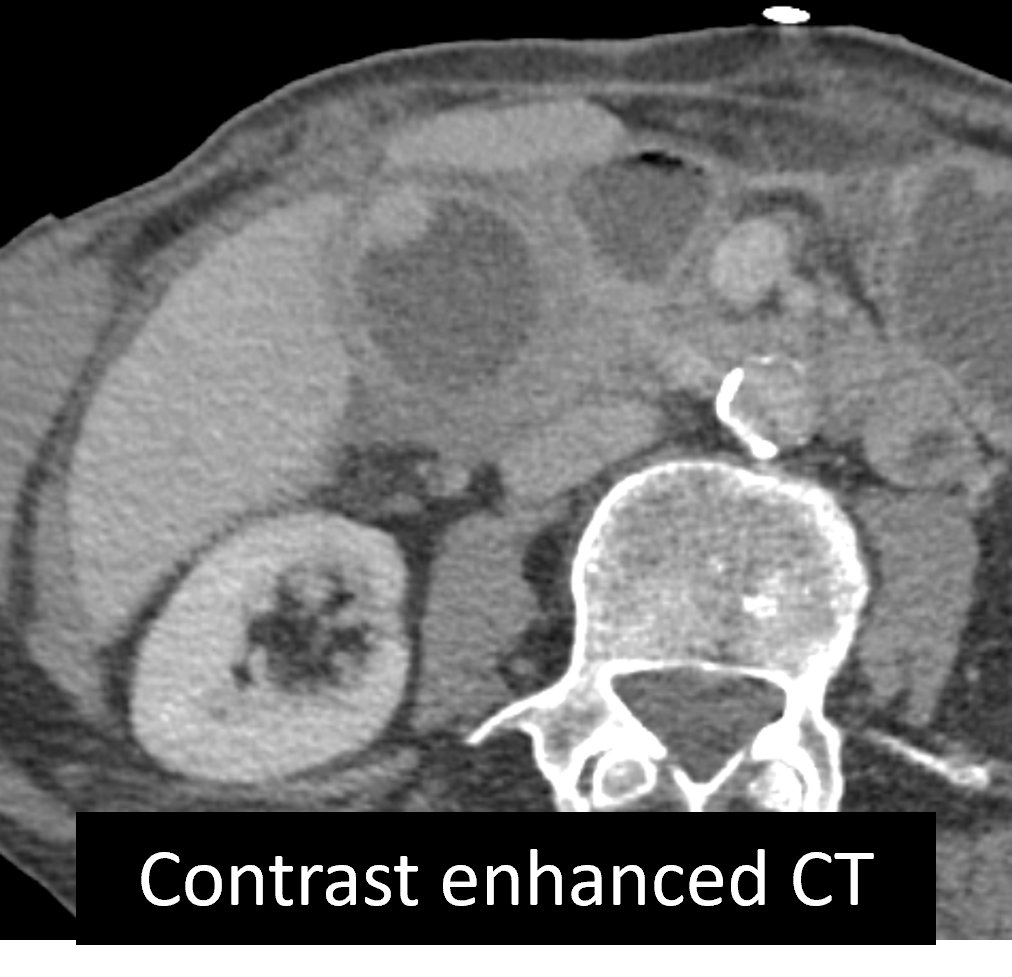

Axial and coronal contrast enhanced CT images demonstrating: Multiple discrete and confluent areas of cystic change within the gallbladder wall which is markedly thickened, continuous enhancement of the mucosa and serosa Answer: Xanthogranulomatous cholecystitis